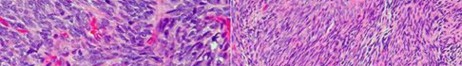

A 15-year-old male presents with deep knee pain awakening him at night. Radiographs show a permeative destructive lesion in the distal femoral metaphysis with a 'sunburst' periosteal reaction and Codman's triangle.

Biopsy confirms high-grade conventional osteosarcoma. What is the most critical prognostic factor for long-term overall survival in this patient?

Explanation

For localized high-grade osteosarcoma, the most important prognostic indicator is the histologic response to neoadjuvant chemotherapy. This is evaluated during the definitive resection. A 'good response' is typically defined as greater than 90% or 99% tumor necrosis. Patients who achieve this level of necrosis have a significantly improved disease-free and overall survival rate compared to 'poor responders' who have extensive viable tumor cells remaining.